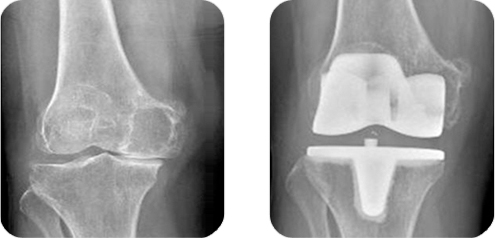

만약 무릎이 관절염 혹은 외상에 의해 손상되었다면 걷기나 계단 오르내리기 등의 간단한 운동을 하기에 불편감을 느끼고 심한 경우 누워있거나 앉아 있을 때 조차 통증을 느끼게 될 것 입니다. 만약 보조기나 약물치료 등의 보존적 치료가 더 이상 효과적이지 않다면 무릎관절 인공관절 전치환술의 수술적 치료가 필요하게 됩니다.

이 수술은 X-선 검사에 퇴행성 관절염이 심하고 약물 치료에 호전이 없는 환자에서 사용할 수 있는 마지막 수술법으로 알려져 있습니다. 인공관절 전치환술은 최초에 1968년에 시행되었고 보형물의 발전과 수술기법의 발전으로 인해 현재는 가장 많이 시행되고 있는 수술 중 하나입니다. 만성 무릎 통증과 장애의 가장 흔한 원인은 관절염입니다. 관절염에 많은 종류가 있지만 대부분의 무릎 통증은 단지 세 가지 유형에 의해 발생합니다.

뼈의 제거 : 대퇴골과 경골의 말단에 있는 손상된 관절 연골을 연골 하방에 있는 뼈의 절편과 함께 제거합니다.

금속 보형물의 위치 : 절제된 연골과 뼈는 금속 보형물로 대체되게 되며 이 보형물이 관절 면을 재형성하게 됩니다. 이 보형물들은 골시멘트를 이용하여 부착할 수 있고 혹은 “press-fit”으로 맞춰 부착되어 고정시키게 됩니다.

슬개골 치환 : 슬개골의 밑면이 절제되고 플라스틱 보형물로 대체되게 됩니다. 환자의 슬개골 관절 연골의 상태에 따라 치환술을 시행하지 않는 경우도 있습니다.

충전물 삽입 : 대퇴골과 경골의 금속 보형물 사이에 플라스틱 충전물을 삽입하게 되며 이로 인해 금속끼리 부드럽게 움직일 수 있게 합니다.